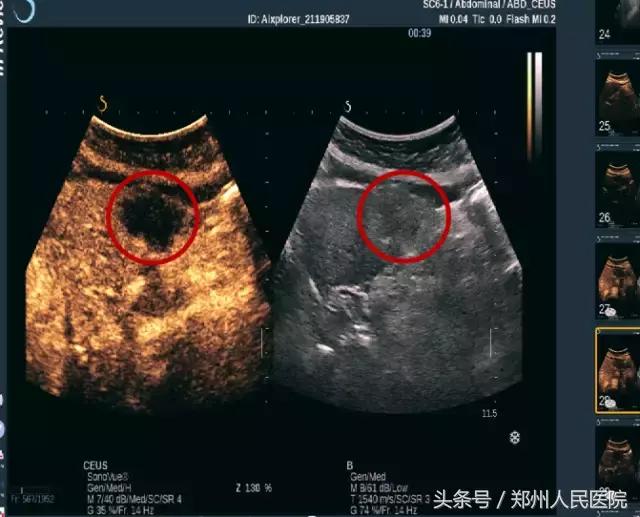

超声医学科王岩青主任耐心解答患者疑惑,提出了利用先进的超声造影技术来鉴别诊断,超声造影可以对肿块内部血流信息清晰显示。通过血管结构变化结合周围图像信息判断肿块良恶性。目前超声造影已经广泛应用于肝、肾、输卵管、乳腺、甲状腺等脏器病变的检查。

超声造影即通过外周静脉注射微泡声学造影剂,利用造影剂使后散射回声增强,明显提高超声诊断的分辨力、敏感性和特异性的技术。

3可以观察病灶血液供应情况 判断肿瘤的良、恶性